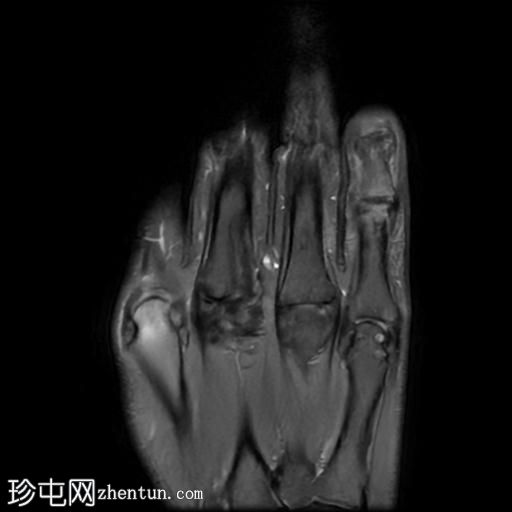

MRI

矢状位

PD脂肪抑制像

轴位PD脂肪抑制像

第五指小指伸肌腱远端纤维完全撕裂,伴远端指间关节屈曲畸形。

撕裂肌腱近端位于第五指中节指骨头附近,止点与近端撕裂处之间约有4毫米的间隙。

患者左手受伤,导致第五指小指伸肌腱远端止点纤维完全撕裂,并伴有槌状指畸形。